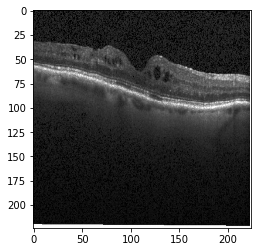

III-B Data Acquisition and Preparation

Optical coherence tomography (OCT) images were selected from retrospective cohorts of adult patients from different hospitals around the world. OCT Images are labeled as (disease)-(randomized patient ID)-(image number by this patient) [11] and Fig 1 shows some examples of OCT images. Image properties are presented in Table II and the distribution of image quantity is presented in Table III. Custom image generators resize images to 224x224x3 and normalize them

Original Image

Original Image

Original Image

Original Image

V MODEL EXPLANATION WITH XAI

Fig 6, 7, 8 and 9 depicts the visualization of correct predictions by our proposed CNN model where fig 6 is class CNV, fig 8 is class DME, fig 7 is DRUSEN and finally, fig 9 is NORMAL. Here the first photo in every class is the original image. The LIME map of our suggested model’s prediction is shown in image B whereas in image C the positive region is highlighted in specific sections on the original image. For Image D we have increased the number of features from 5 to 10 thus more regions have been predicted as the positive region which is highlighted in green. After increasing the features from 5 to 10, some of the regions are predicted wrongly. The red regions represent the output of incorrect prediction. The following image represents the Grad-CAM heatmap highlighting the regions with our model’s prediction.